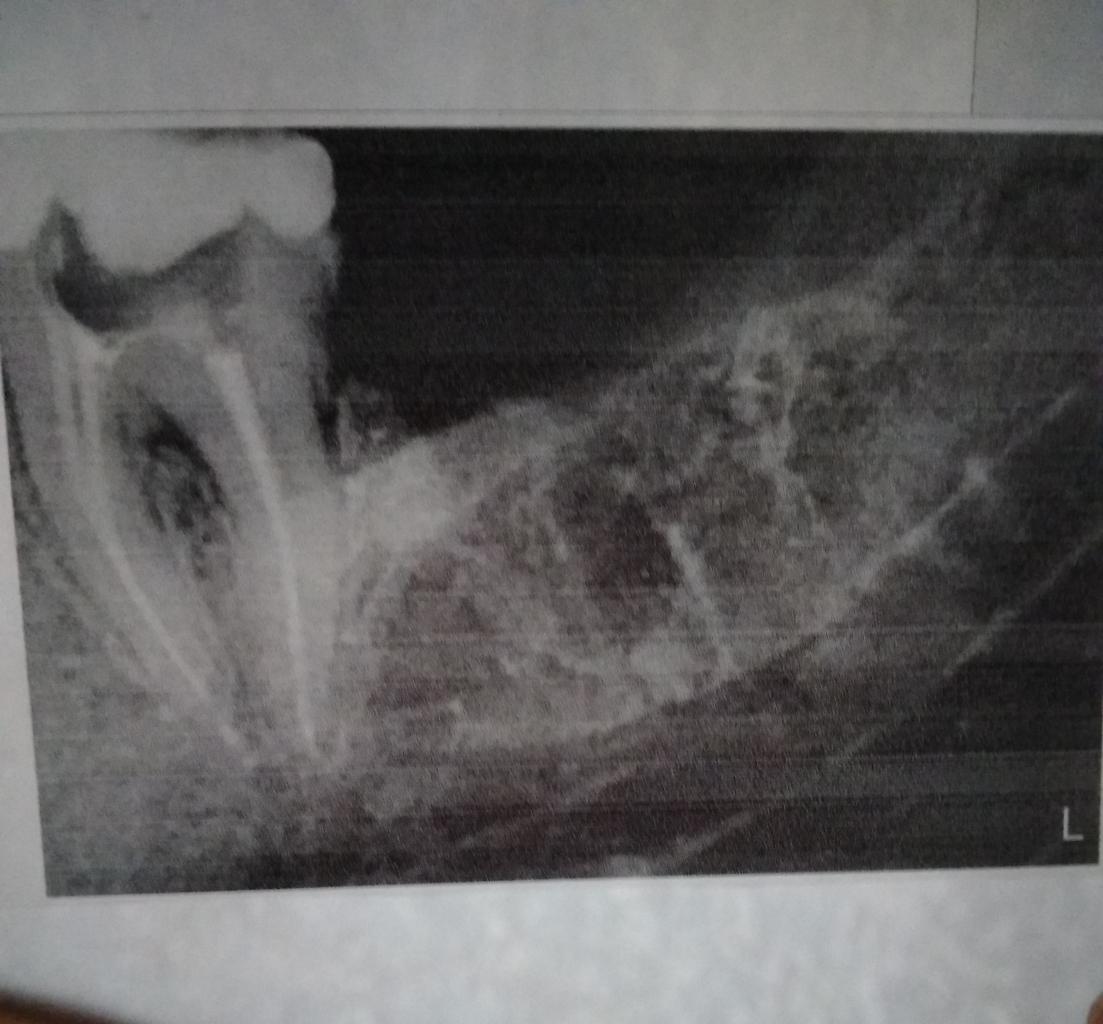

Доброе утро. В субботу удалила зуб мудрости справа внизу. Он сразу лез чёрный и как то в бок, полностью так не вылез, часть осталась под десной и десна начала напухать. На снимке было видно, что корень был в виде запятой. Во время удаления зуб поломался и доктор доставал его по частям. Десну зашили, сейчас осталась слегка заметная припухлость. Антибиотик пропила. Но к вечеру у меня начинает болеть. Сначала несильно, боль ноющая. Думала, может сегодня ночью обойтись без обезболивающих, а нет среди ночи начал ныть правый нижний ряд зубов . Это может быть или что-то не то? Я завтра и так собиралась посетить доктора. Но здесь нашла неоднозначные отзывы про него. Стоит ли беспокоиться и бежать на Ришельевскую? Или такая ноюшая боль бывает до окончательного заживания десны?